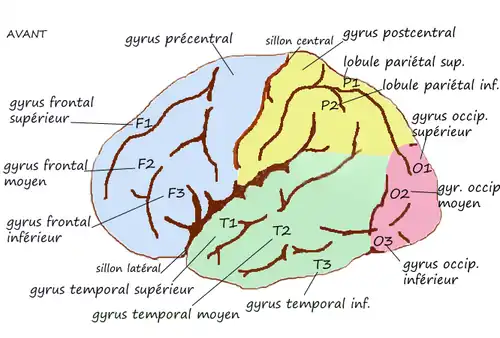

Le gyrus précentral ou circonvolution frontale ascendante est un gyrus de la face latérale du lobe frontal du cortex cérébral, limité en avant par le sillon précentral et en arrière par le sillon central de Rolando.

| Face externe de l'hémisphère gauche |